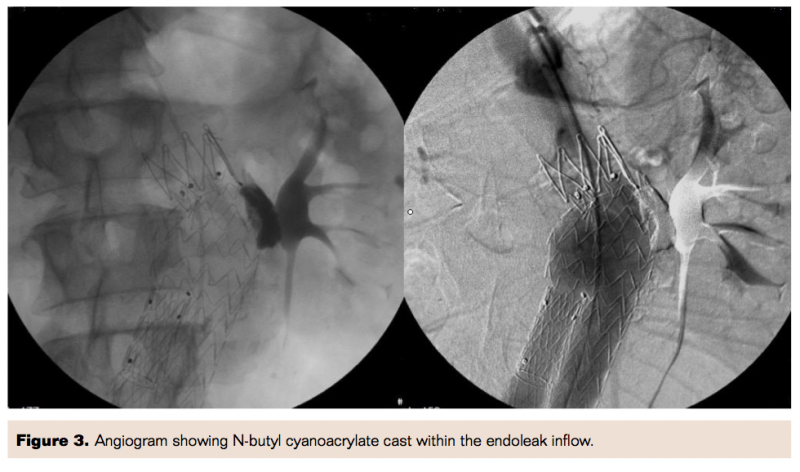

For selective catheterization of the aneurysm sac, over a 0.035˝ guidewire, a 5 Fr Simmons Imager II catheter (Boston Scientific) was introduced between the proximal stent-graft attachment site and the aortic wall. By using manual injection of contrast, the origin of the type IA endoleak was evaluated. A 2 Fr Excelsior 1018 microcatheter (Boston Scientific) was advanced coaxially through the 5 Fr catheter into the endoleak inflow and a selective angiogram of the aneurysm sac was performed (Figure 2). A mixture of 0.5 mL of Histoacryl NBCA resin (B. Braun) and 3.5 mL of Lipiodol oil-based iodine contrast (Guerbet) was prepared. The microcatheter was flushed with 5% dextrose solution to prevent premature precipitation of NBCA. Under continuous fluoroscopic guidance, a total of 3 mL of 12.5% NBCA solution was injected slowly through the microcatheter for 25 seconds; meanwhile the catheter was gradually withdrawn toward the leading edge of the graft to form a cast within the endoleak inflow (Figure 3). Both catheters were withdrawn from the patient within seconds before complete polymerization could occur.